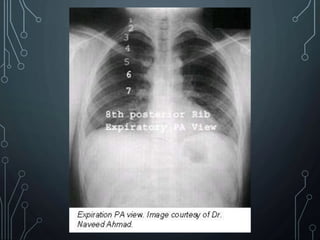

• An expiratory film may be helpful under some

circumstances.

• A small pneumothorax (air in the pleural cavity)

may be difficult to detect on a routine inspiratory

PA film.

• On expiration, the volume of the thorax and lungs

is reduced but the amount of air in the pleural

space remains essentially unchanged.

• The pneumothorax then occupies a larger

percentage of the area of the thorax and is more

easily visible.